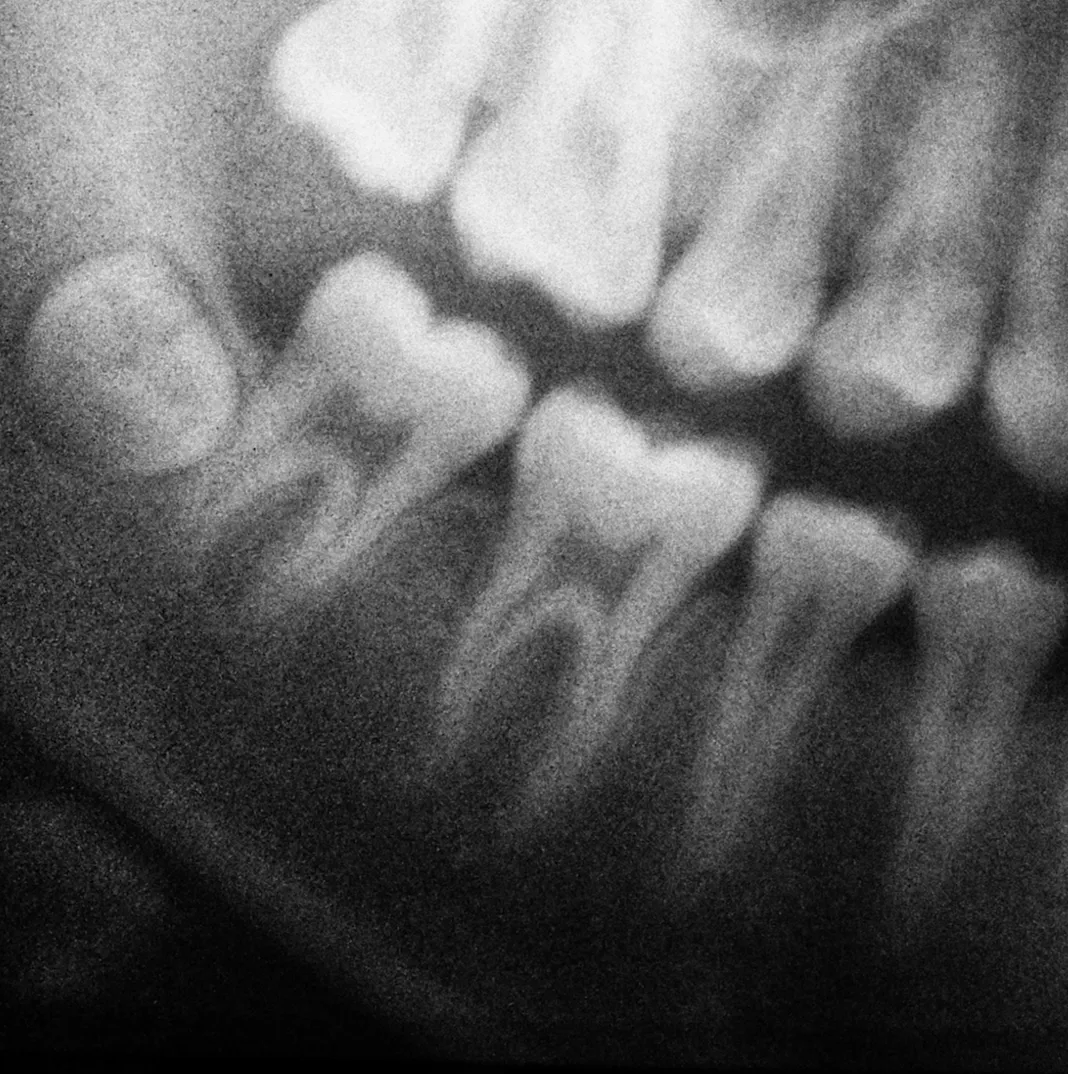

Advanced Dental Technology

At Concord Heritage Dental, we use cutting-edge dental technology to make your visits more comfortable, precise, and informative. By combining digital imaging, intraoral cameras, and digital scanners, we can see details that aren’t visible with the naked eye, diagnose problems earlier, and create personalized treatment plans with confidence. These tools not only enhance your care but also allow you to better understand your oral health and the recommended treatments.